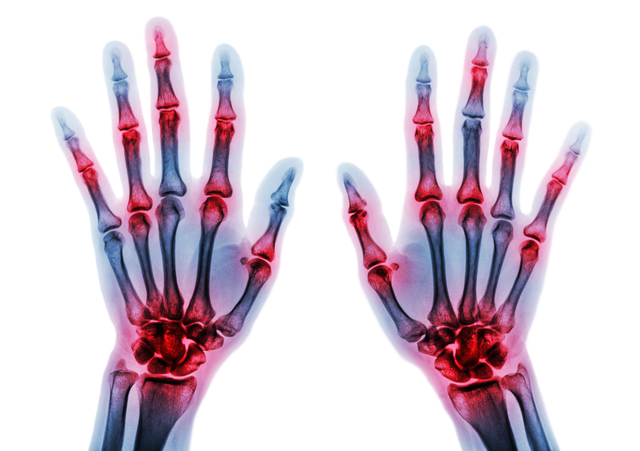

| 影響を受ける関節 | 通常、小さな関節、特に指から始まります。症状は対称的(体の両側)であり、後に大きな関節に発症する可能性があります。 | 多くの場合、手と指の関節ですが、RA よりも対称性が低くなります。膝、背骨、腰にも影響を与えます。 |

関節リウマチは対称性の病気です。つまり、体の両側に同時に症状が現れる可能性があります。